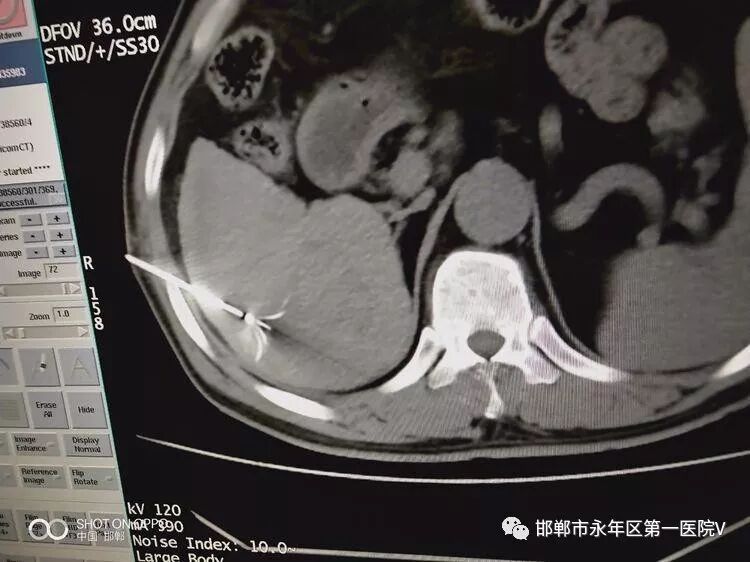

2019年10月19日在CT室行CT引导下原发性肝癌射频消融术!术中射频消融针精确穿刺到肿瘤中心,并展开子针包绕肿瘤并扩大消融范围,加热至90℃持续消融约10分钟。感谢CT室同事们的大力支持及积极的配合!

手术医师精准的操作中!

行2次叠加消融达到完全根治肿瘤的目的,术后扫描可见肿瘤完全坏死及周边安全范围低密度晕,手术成功!!!